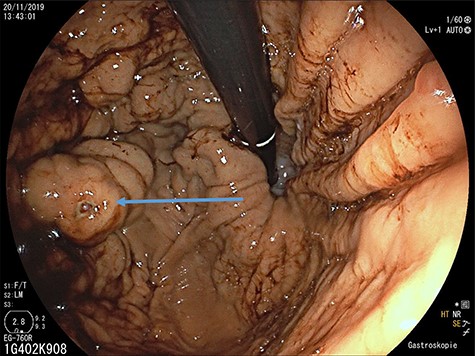

Portal venous phase CT of the upper abdomen (a) with a 3D reconstruction (b); note the gastric varices (arrowhead) and dilatation of short gastric veins (solid arrow) and coronary vein (dashed arrow); St: stomach; Spl: accessory spleen.

was located in the left upper quadrant of the abdomen, nearly adherent to the stomach and a moderate variceal conglomeration in the fundus of the stomach (Fig. 2). Liver cirrhosis or portal vein occlusion and other inflammatory or malignant diseases could be excluded from CT imaging. In addition, a CT scan was able to show clearly that the arterial blood supply of the accessory spleen is derived from the short gastric arteries. Splenic artery and vein could not be delineated. The patient was subsequently presented to our Department of Visceral Surgery. We decided to perform laparoscopic accessory splenectomy to relief the regional hypertension of the short gastric veins. In the operation room, the patient was positioned in right semi-decubitus position. One 12 mm Trocar, two 11 mm Trocars and on 5 mm Trocar were inserted in the left upper quadrant. The accessory spleen was extremely adherent to the diaphragm and retroperitoneal tissue (Fig. 3). After transection of the short gastric vessels with the vessel sealer (Ligasure™, Medtronic, Germany), the spleen was mobilized and removed (Fig. 4). Patient’s postoperative course was completely uneventful, and he was discharged in good health condition on the seventh postoperative day. The diagnosis was confirmed by immunohistologic examination (Fig. 5).